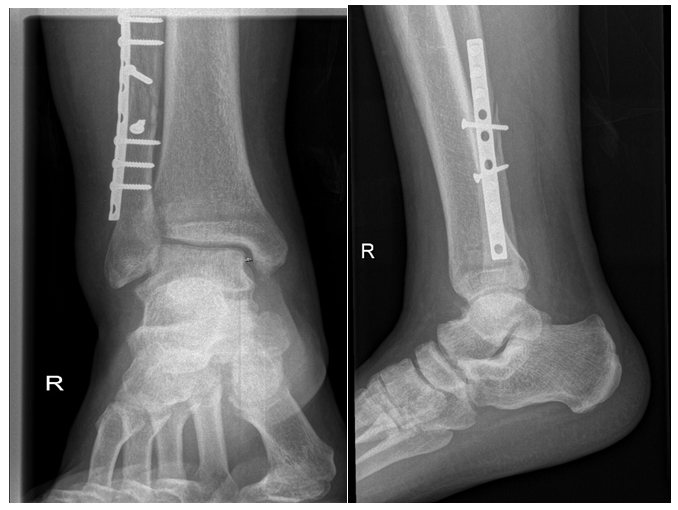

Primary right Ankle X-rays done at trauma bay (Figure 1). AP and lateral X-rays of right ankle showing after fixation (Figure 2). After 8 weeks patient underwent synedsmotic screw removal (Figure 3), and he noticed big toe deformity. At 1 year follow up patient booked for implant removal and was still complaining of same deformity and underwent FHL lengthening at same time.

Figure 3 Synedsmotic screw removal and noticed big toe deformity.

After 6 weeks patient noticed big toe flexion contracture (Figure 4) and started on splinting and stretching as treatment. At 8 weeks syndesmotic screw removed and he continued on conservative treatment for 1 year with no improvement of deformity. Then he underwent surgery for implant removal and midfoot FHL lengthening (Figure 5). Patient was followed for 2 month after surgery with full correction of the deformity.